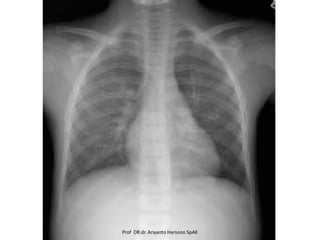

Prof DR.dr. Ariyanto Harsono SpAK

X-Linked Agammaglobulinemia

X-Linked Agammaglobulinemia (XLA) is an

inherited immunodeficiency in which the body

is unable to produce the antibodies needed to

defend against bacteria and viruses.